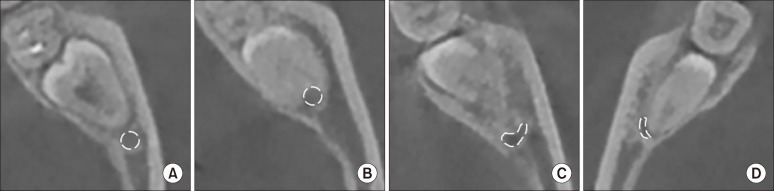

Objectives: : Many three-dimensionally-evaluated difficulty indices for impacted third molars have been suggested; however, their radiological and clinical validation according to the inferior alveolar nerve (IAN) remains unknown. This study aimed to evaluate the association of the difficulty index with IAN proximity and injury risk.

Materials and methods: : We retrospectively enrolled patients with cone-beam computed tomography (CBCT) for a fully impacted mandibular third molar from January to December 2020. We evaluated the third molar according to the difficulty index based on panoramic x-ray and the nerve index based on CBCT and analyzed postoperative nerve complications. The relationships among nerve proximity, difficulty indices, and nerve complications were evaluated. Data were analyzed using the Pearson's chi-square test and the Cochran-Armitage test for trends.

Results: : We included 367 subjects (177 males, 28.9±9.8 years) with follow-up of at least 1 month. Twenty-two subjects had nerve complications. Radiologic evaluation showed that third molars with a high nerve index had an increased difficulty index (P=0.001). Nerve complication risk showed a statistically significant correlation with both nerve and difficulty indices.

Conclusion: : In conclusion, the difficulty index of an impacted third molar was valid in terms of its spatial relationship with the IAN and in predicting nerve complications.